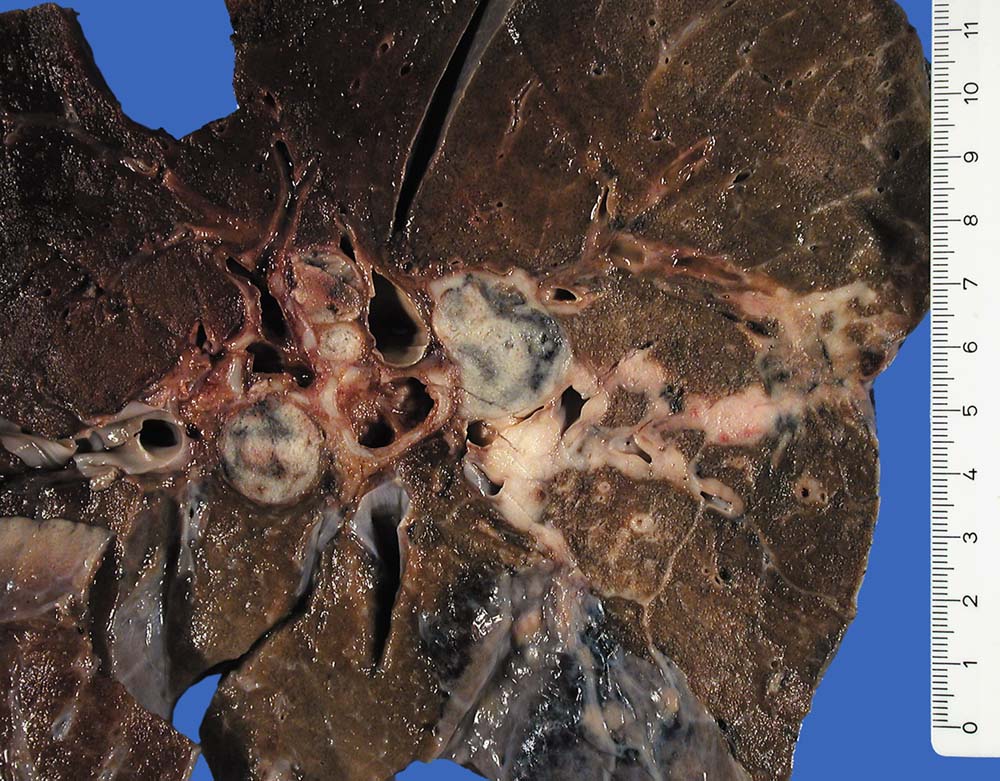

PathoPic ID 8838 - Kleinzelliges Bronchuskarzinom

Kleinzelliges Bronchuskarzinom

maligner Tumor

Lunge

Peribronchiales grauweisses Tumorinfiltrat und Lymphangiosis carcinomatosa. Das umgebende Lungenparenchym zeigt eine Bronchopneumonie.

Kleinzelliges Bronchuskarzinom bekannt seit 5 Monaten

Makroskopie

41

männlich